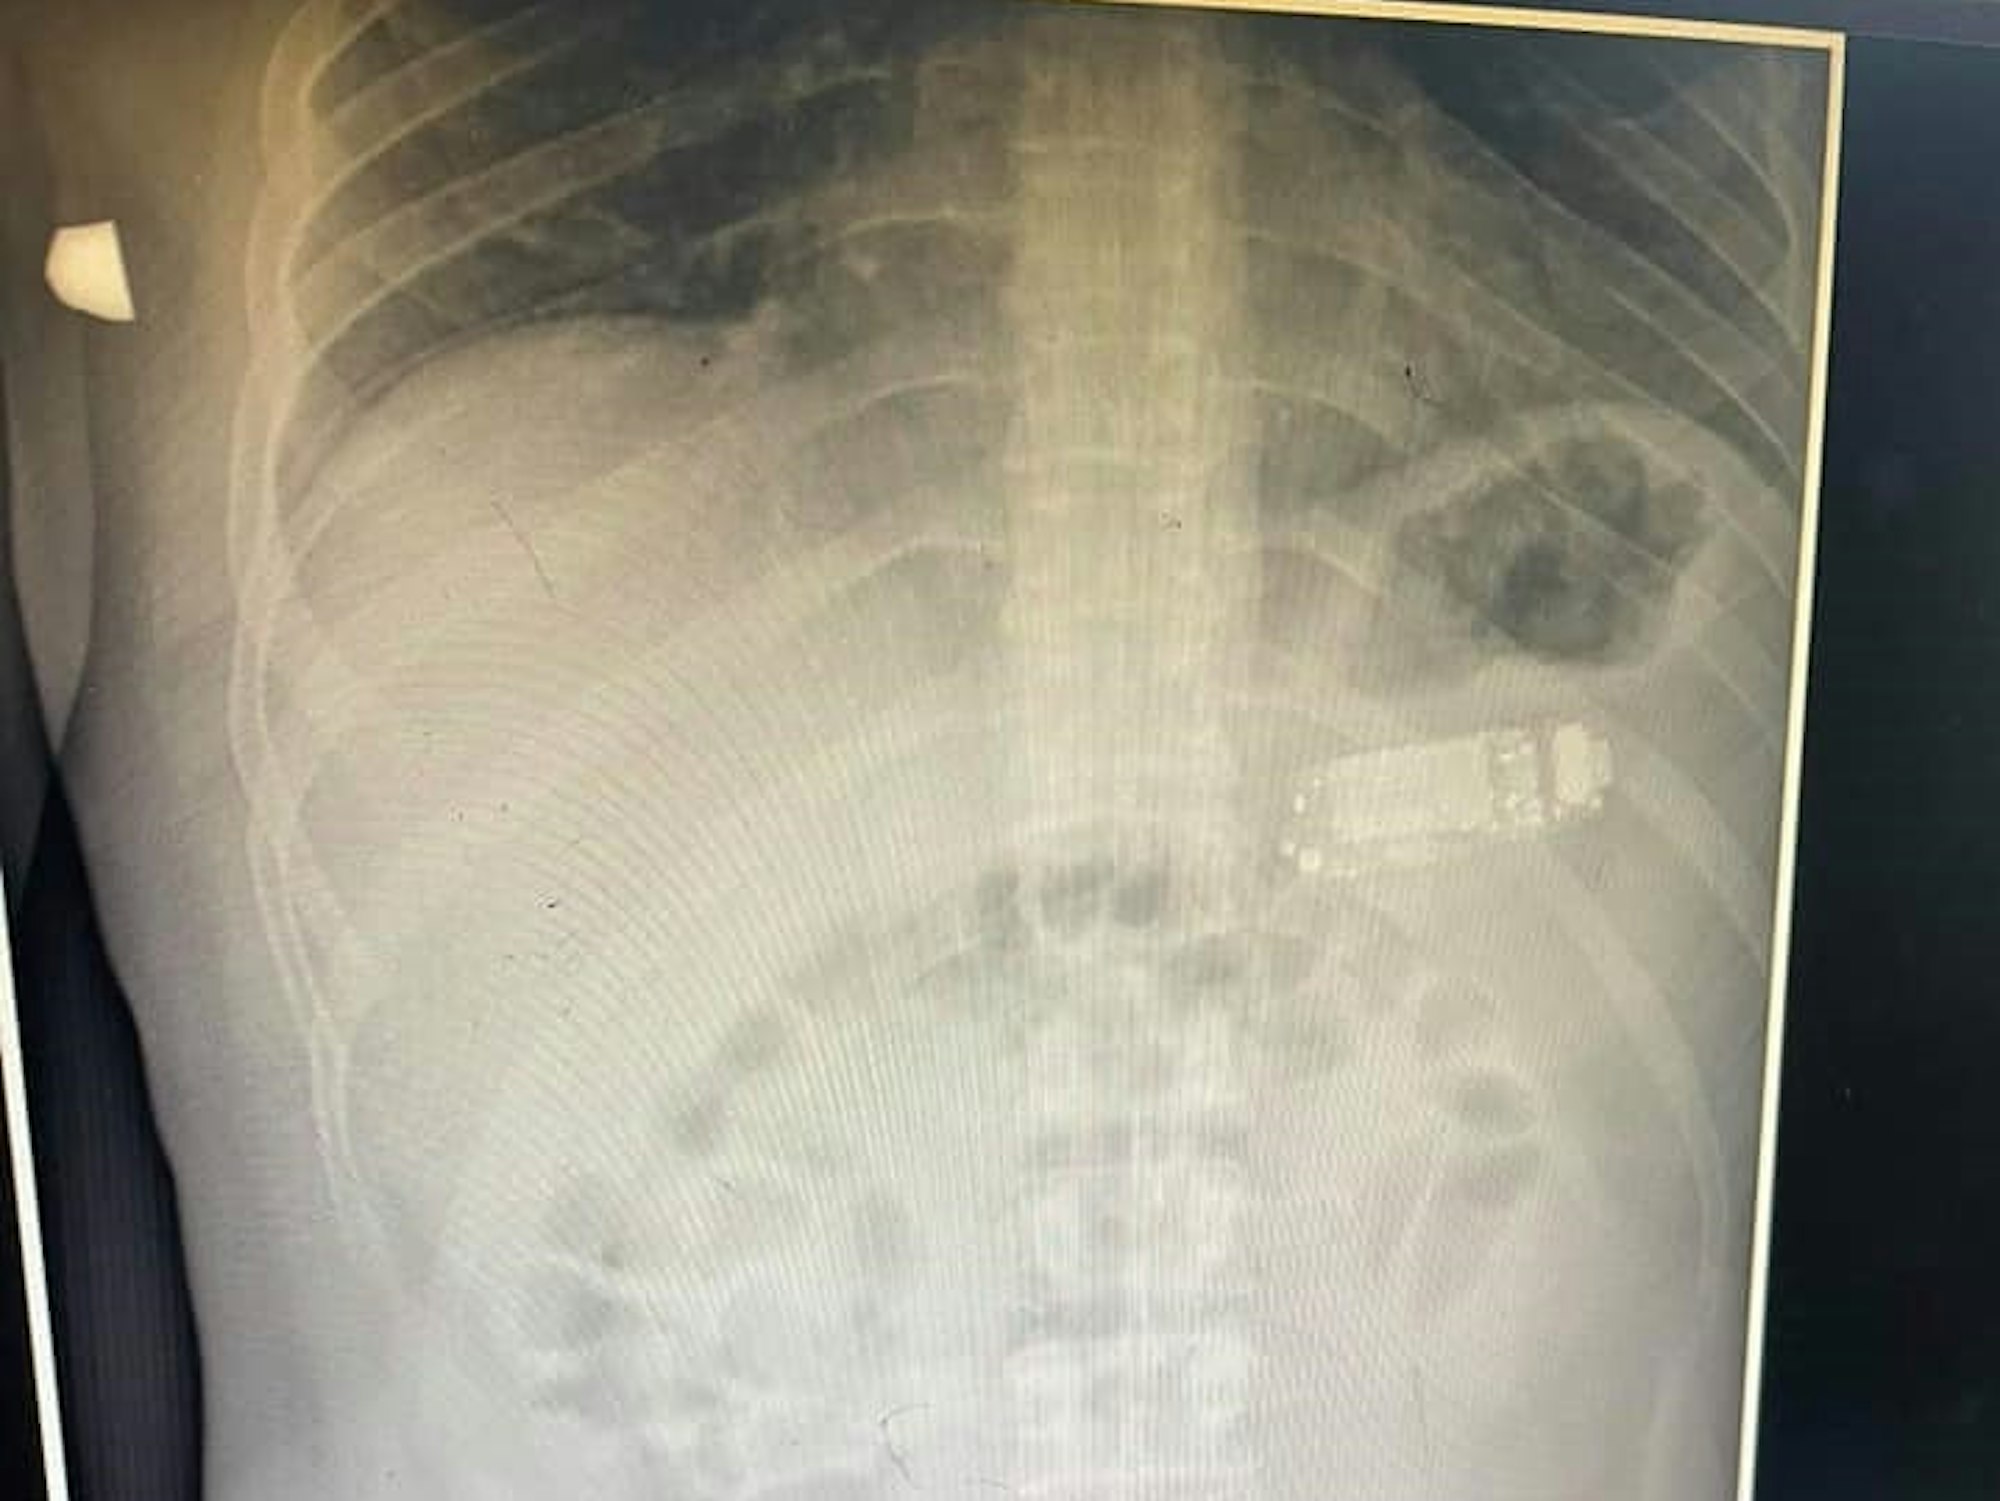

Mediziner Skender Telaku postete das Röntgenbild von einem Patienten mit Handy im Magen auf Facebook.

Als der Mediziner die Röntgenbilder begutachtete, traute er vermutlich seinen Augen nicht. „Wir stellten fest, dass er ein Handy im Magen hatte“, berichtet Telaku.

Von allen Teilen des Handys war es die Batterie, welche die behandelnden Ärzte am meisten beunruhigte, weil sie im Magen des Mannes hätte explodieren können. Zudem enthalten Akkus giftige Schadstoffe, die tödlich sein können, wenn sie in den menschlichen Organismus gelangen.

Bei dem Handy handelt es sich demnach um ein Nokia 3310. Das Kult-Gerät kam im Jahr 2000 auf den Markt und galt als unzerstörbar. Ein Umstand, der dem 33-Jährigen möglicherweise das Leben gerettet haben könnte.

Dennoch galt es, das Telefon natürlich schnellstmöglich aus dem Magen herauszubekommen. Um den Eingriff so minimalinvasiv wie möglich zu gestalten, zerlegte der routinierte Arzt das Handy in seine drei Einzelteile, um sie dann durch den Darmwindungen zu entfernen – nämlich durch den Mund.